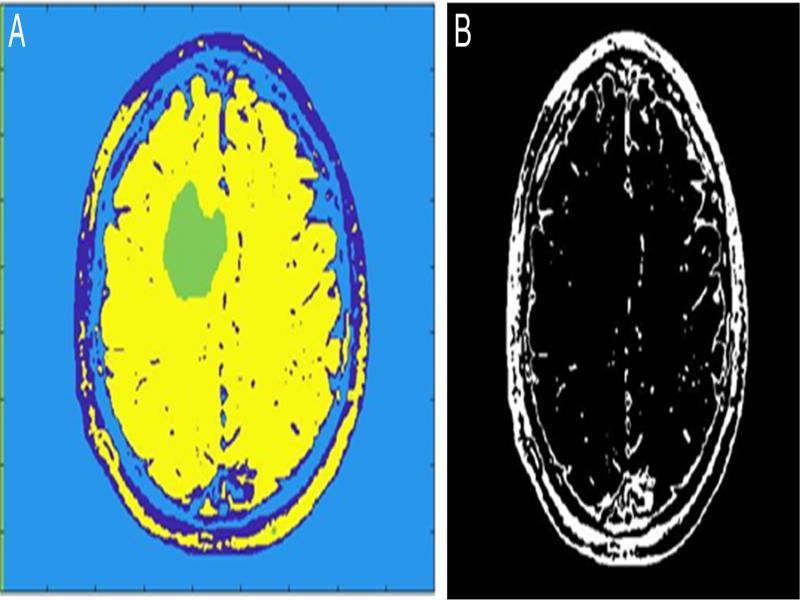

The outcome of the proposed methodology is seen in figure 9. Figure 8 represents the input image and figure 9 is the processed image with the highlighted tumor region.

Figure 8:

Input image.

Figure 9:

Output image.

A distinct highlighted tumor region is visible in the final output image.